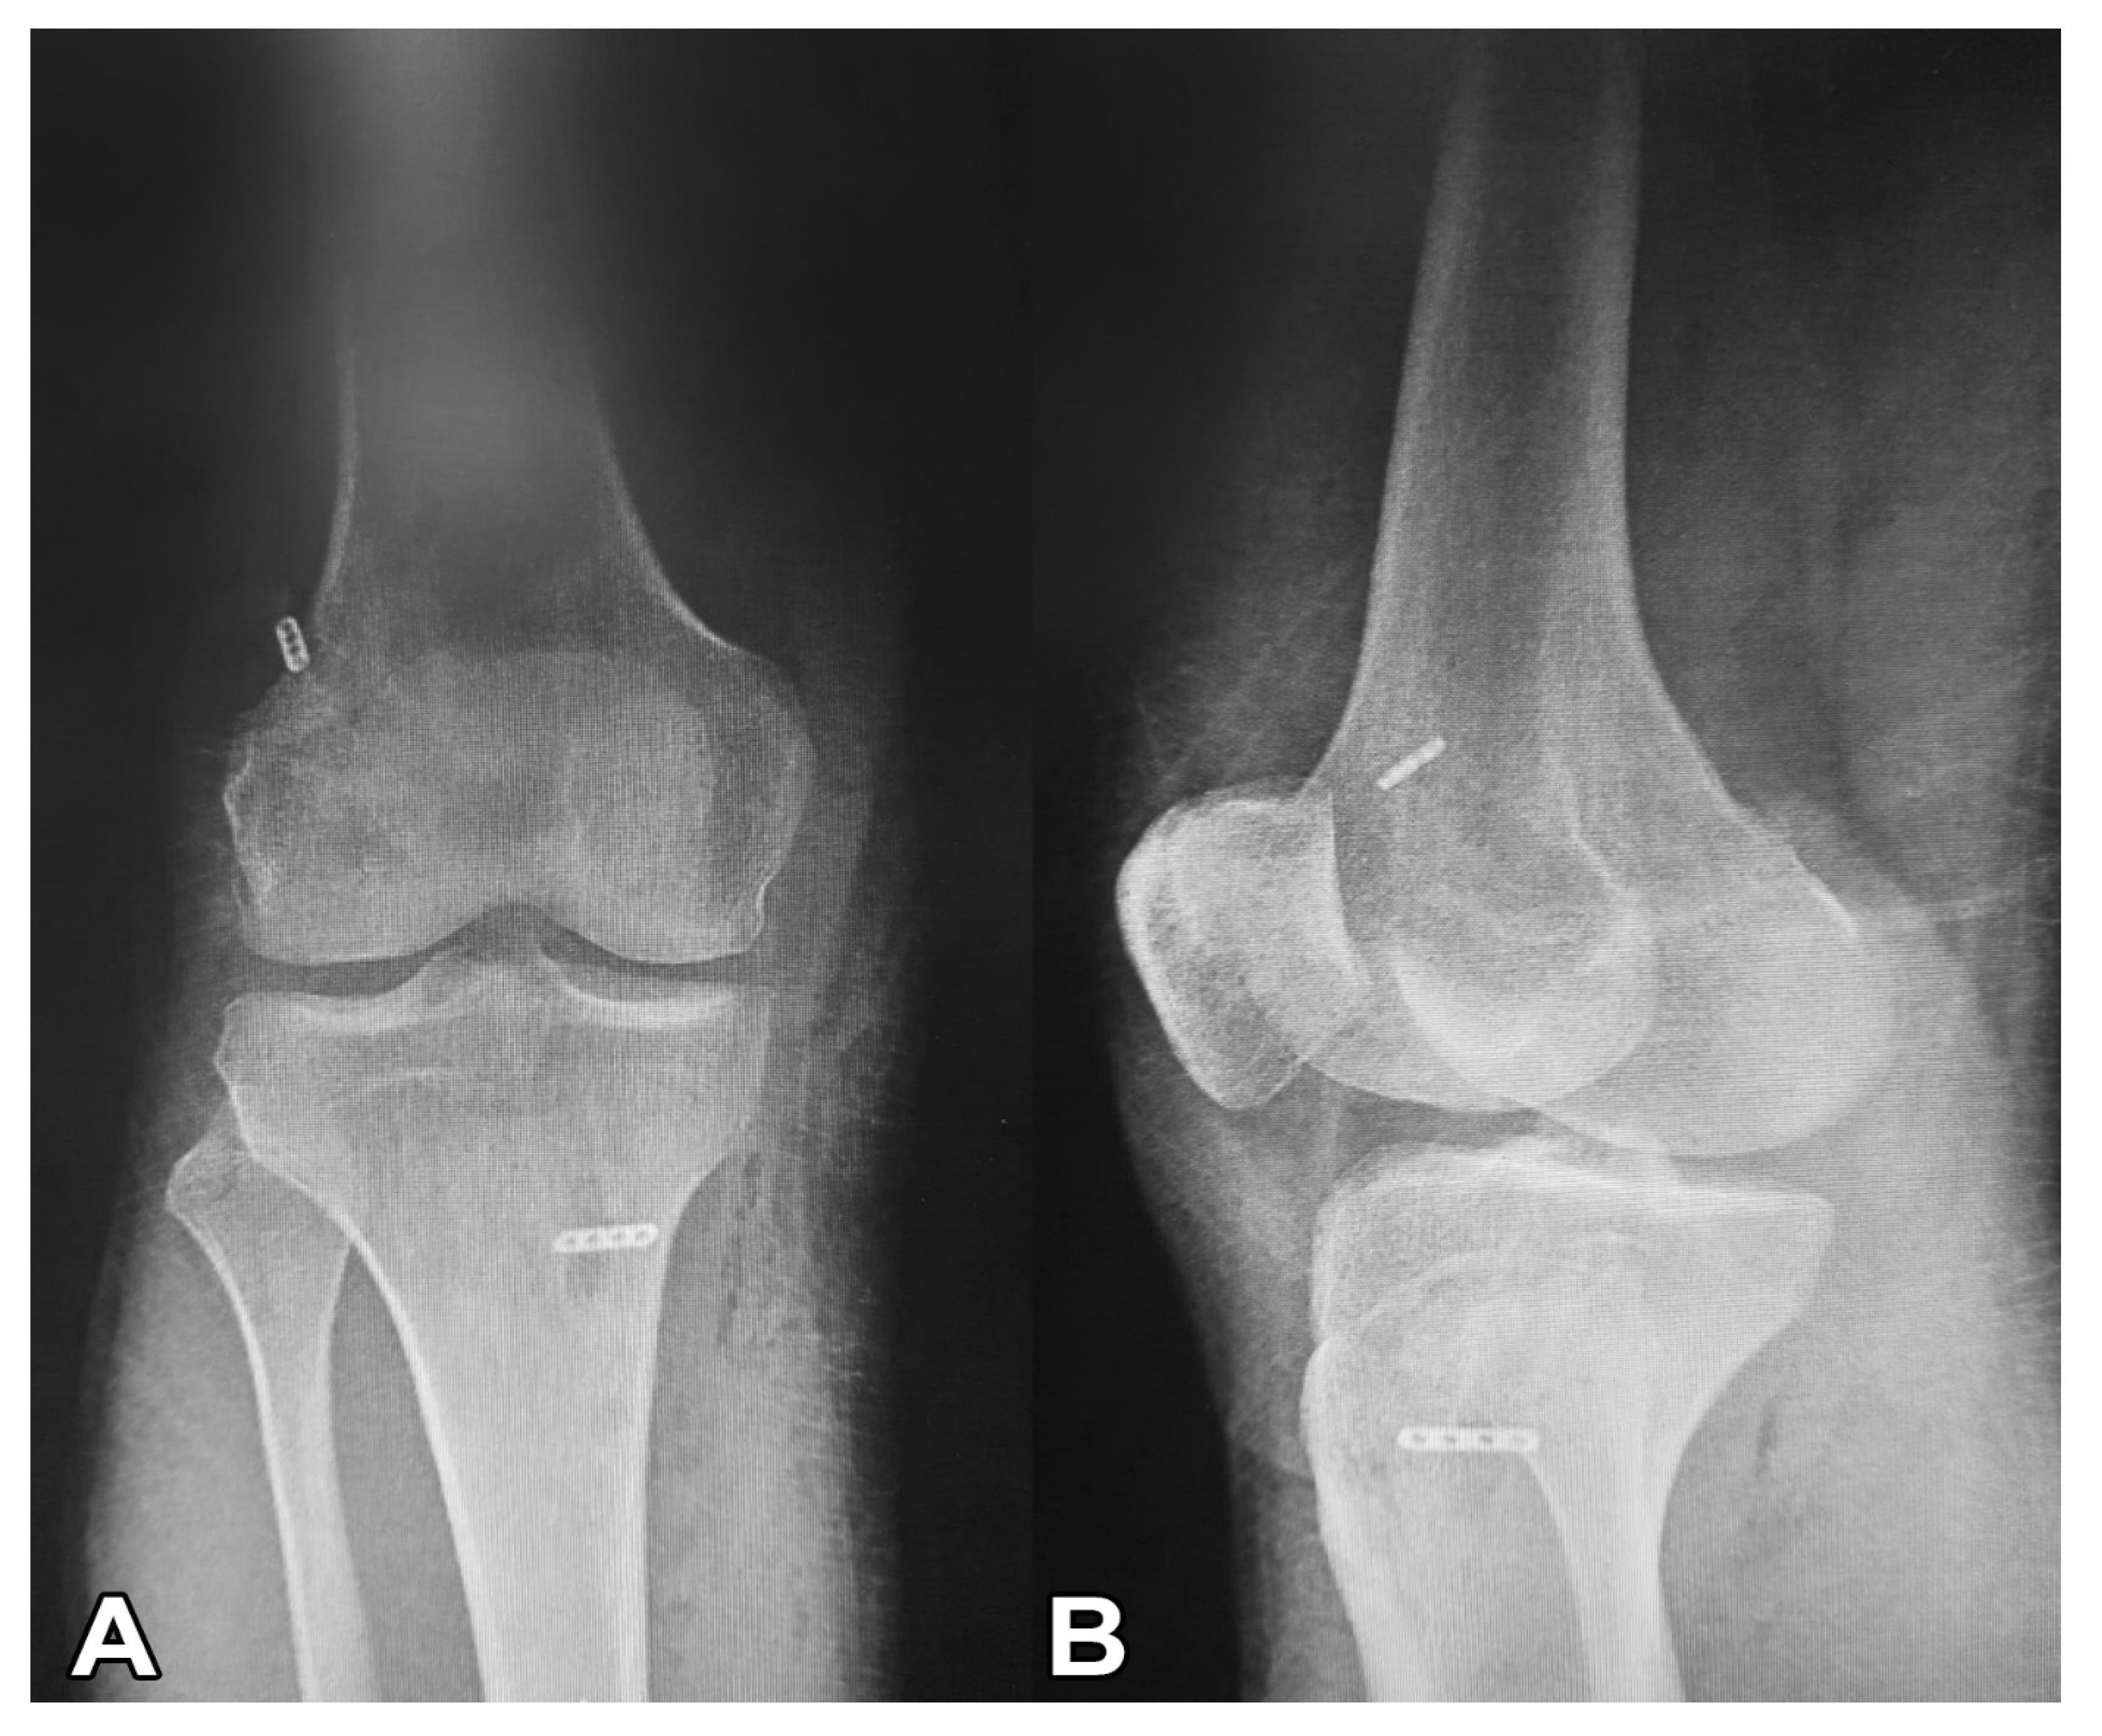

2.2. Surgical Treatment (Modified All-Inside Technique)